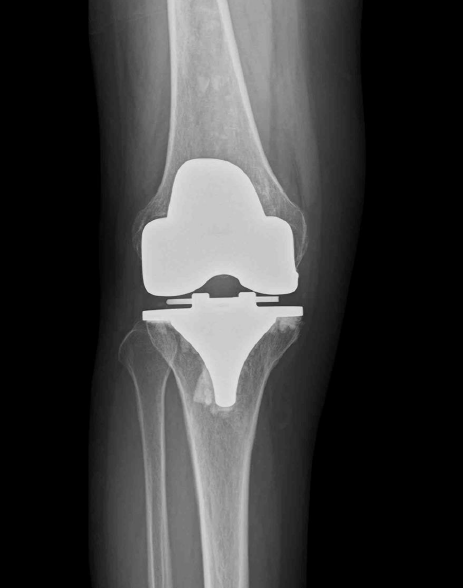

変形性膝関節症(KOA)は、軟骨の変性により痛みや可動域制限を引き起こす疾患です。重症の場合、人工膝関節置換術(TKA)が行われますが、実は手術から24ヵ月が経過しても、約15%の症例で膝の痛みが残存するという報告があります。

【症例:73歳女性】 5年前から右膝痛が出現し、3年前に人工膝関節置換術(TKA)を施行。しかし術後も痛みに変化がなく、歩行にも支障をきたしていました。